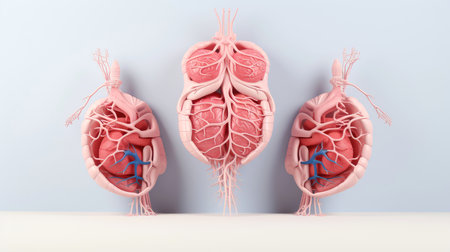

3D illustration mockup of the human organ system, Anatomy, Nervous, circulatory, digestive, excretory, urinary,and bone systems. Medical education concept, Generative AI illustration

3D illustration mockup of the human organ system, Anatomy, Nervous, circulatory, digestive, excretory, urinary,and bone systems. Medical education concept, Generative AI illustration

3D illustration mockup of the human organ system, Anatomy, Nervous, circulatory, digestive, excretory, urinary,and bone systems. Medical education concept, Generative AI illustration

3D illustration mockup of the human organ system, Anatomy, Nervous, circulatory, digestive, excretory, urinary,and bone systems. Medical education concept, Generative AI illustration